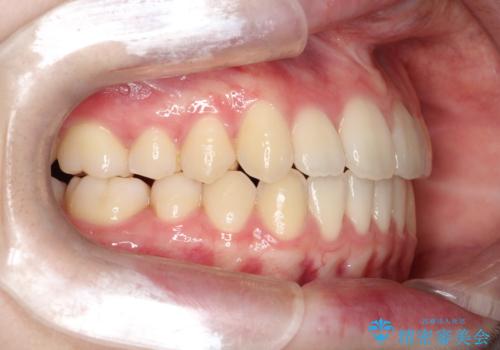

【インビザライン】前歯のガタガタをなおしたい

- 前歯のガタガタを主訴に来院されました。

開咬ぎみであったため、しっかりと前歯が噛むように計画を立てて治療をおこないました。

仕上がりも良く、患者様にも満足していただきました。

インビザラインは前歯を噛ませるような開咬の治療も得意としています。